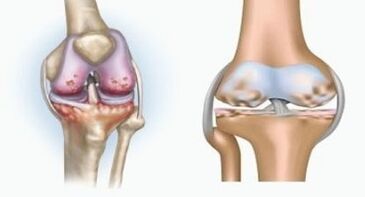

Both pathologies influence the joints, but differ in the type of changes.

With arthritis

Arthritis is an inflammation of the connective tissue - a synovial membrane that contains many vessels and delivers lymphatic current.The inflammatory process leads to a violation of the diet of joint tissues, the production of joint lubrication - synovial fluid is limited.

Osteoarthritis

Osteoarthritis is a degenerative-dystrophic process associated with the destruction of the cartilage tissue of the joint.The cartilage is gradually destroyed, dry, the distance between the articular bones decreases, which is the cause of pain.The destruction influences bones in severe forms.They become porous, lose their density, become fragile.